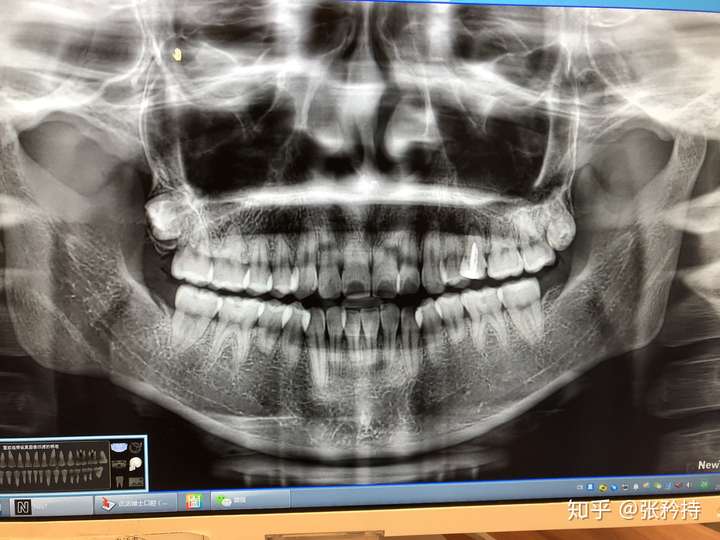

牙根短 牙骨槽薄 有没有情况一样的牙友

我是不是牙根比较短

想问下大家我的牙根短吗